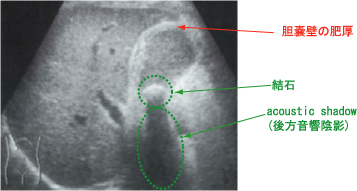

<画像診断>

エコーが有用で、腫大した胆嚢、肥厚した胆嚢壁、結石等が見られます。

(98回医師国家試験D29)